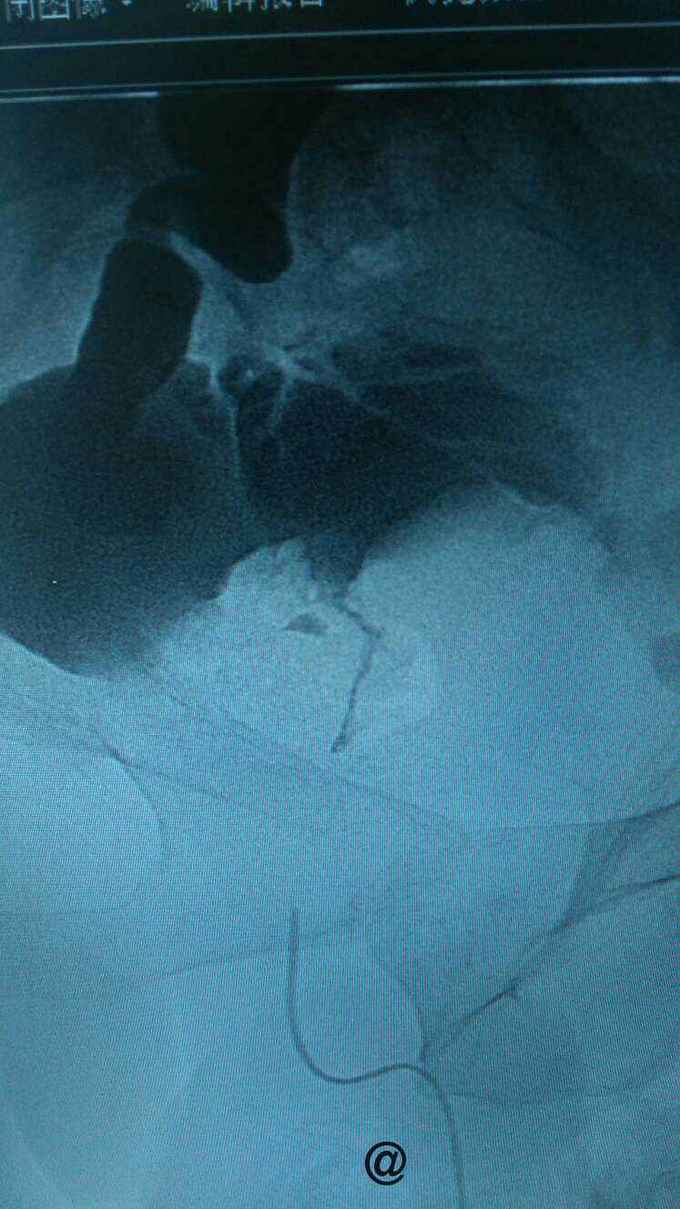

查膀胱镜发现后尿道狭窄,无法进入膀胱。 尿道造影:尿道狭窄,输尿管逆流。嘱咐病人排尿时,膀胱内尿液减少,进入输尿管,肾盂。 肾功能正常。

诊断:尿道狭窄,输尿管逆流 治疗:输尿管镜下探查,见尿道狭窄,膀胱内景清晰,广泛房小梁形成,右侧膀胱后壁可见广口凹陷,输尿管镜置入,可向上探查,实为输尿管,管腔宽大,输尿管镜进出自如,未见占位病变,向膀胱内置入导丝,沿着导丝留置导尿管扩张尿道。